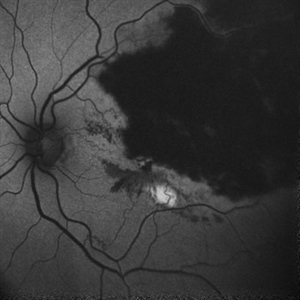

RPE rip in a case of Idiopathic polypoidal choroidopathy RPE rip in a case of Idiopathic polypoidal choroidopathyOct 23 2022 by Anjana Mirajkar, MS Ophthalmology Montage of Fluorescein angiography in a of 61 year old male with RPE rip in a case of Idiopathic Polypoidal Choroidopathy. Photographer: Dr. Anjana Mirajkar -Retina Foundation, Ahmedabad Condition/keywords: Idiopathic polypoidal choroidopathy, RPE rip